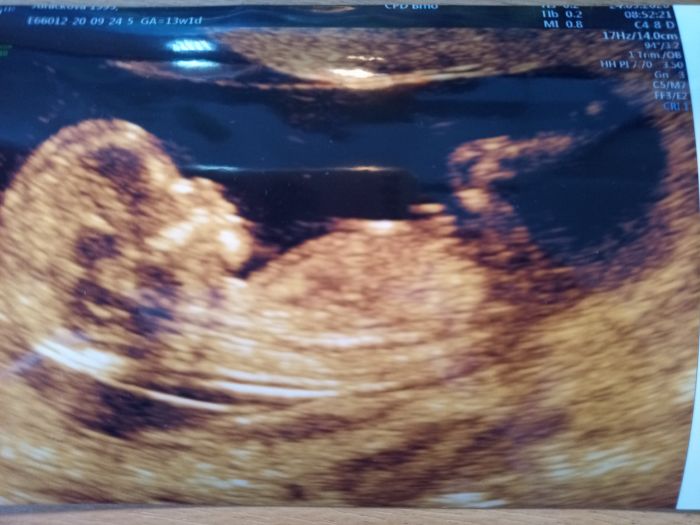

[1142237]jednu mi vytiskli na místě a jinak všechny mailem, prej je to standart